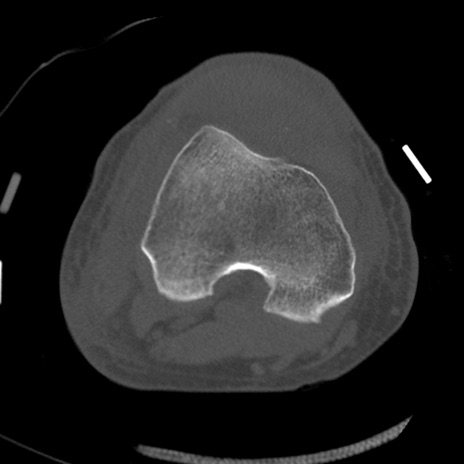

症例28 右膝関節CT(横断像)

右膝関節CT